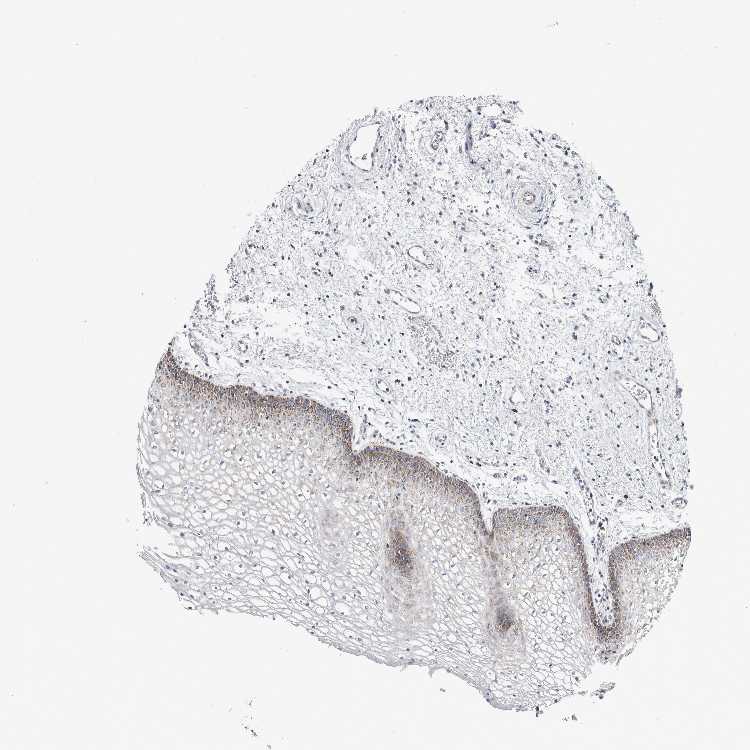

TISSUE PRIMARY DATA VAGINA Show tissue menu

VAGINA - Antibody stainingi

Antibody staining in the annotated cell types in the current human tissue is reported as not detected, low, medium, or high, based on conventional immunohistochemistry profiling in selected tissues. This score is based on the combination of the staining intensity and fraction of stained cells.

Each image is clickable and will lead to virtual microscopy that enables deeper exploration of all samples and also displays staining intensity scores, fraction scores and subcellular localization as well as patient and tissue information for each sample.

Antibody HPA018990Antibody HPA018993Antibody HPA018996Antibody HPA024089

Squamous epithelial cells MediumNot detectedNot detectedLow